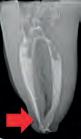

We recommend the following steps for professional whitening evaluation and treatment.

Evaluate the origin of tooth staining and check for restorations that could affect the final result (use X-Ray if needed). Assess the intention of whitening system (cosmetic for generic “day-by-day” discoloration; medical devices for teeth discolored by disease, injury or medical treatment). Consider amending your periodical medical history by adding a question about the patient’s satisfaction with their oral esthetics. Explain to the patient that restorations will not whiten, and discuss the possible need for new restorations after whitening. Check existing sensitivities, and perform an adequate treatment before starting a whitening procedure. Pregnant or breastfeeding women should not whiten. Patients with serious health concerns should consult their primary care provider prior to treatment. Cosmetic teeth whitening treatments are not permited under the age of 18.

Determine origin of staining, evaluate gingival and dental health. Check for restorations in the esthetic zone that may not match after whitening. Discuss changing them out or resurfacing after whitening.